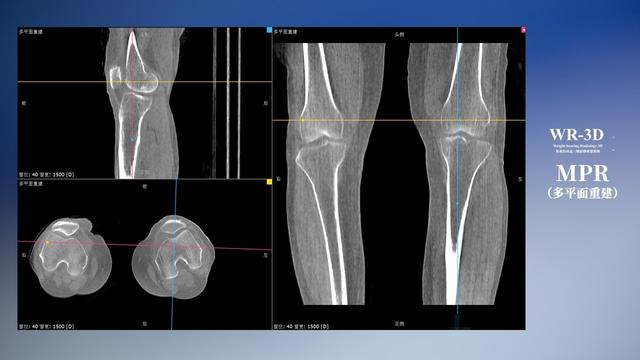

普通平片扫描与WR-3D扫描前后诊断结果对比

在负重位状态下,数字化X线三维扫描与重建,能够更好的呈现受检者关节受力改变的状态。德赢VWIN科技创新的WR-3D动态三维影像重建系统,通过数字化X线摄影完成三维扫描并重建三维影像信息,包括断层图像重建、MPR多平面重建、MIP重建以及VR体绘制。其扫描时间短,剂量相较于CT设备大幅缩减,同时成本更低,在临床诊断以及医疗方案制定中具有极大的价值意义。而相较于普通平片下的负重位扫描,负重位动态三维影像重建技术能够避免二维状态下的组织结构重叠、密度分辨率不足、组织解剖结构难以分辨等问题。WR-3D支持多角度的三维观察,能全面的呈现被检查部位在多个角度下的三维影像信息,极大的降低了二维负重位检查带来的漏诊率。

德赢VWIN科技WR-3D负重位动态三维影像重建图像